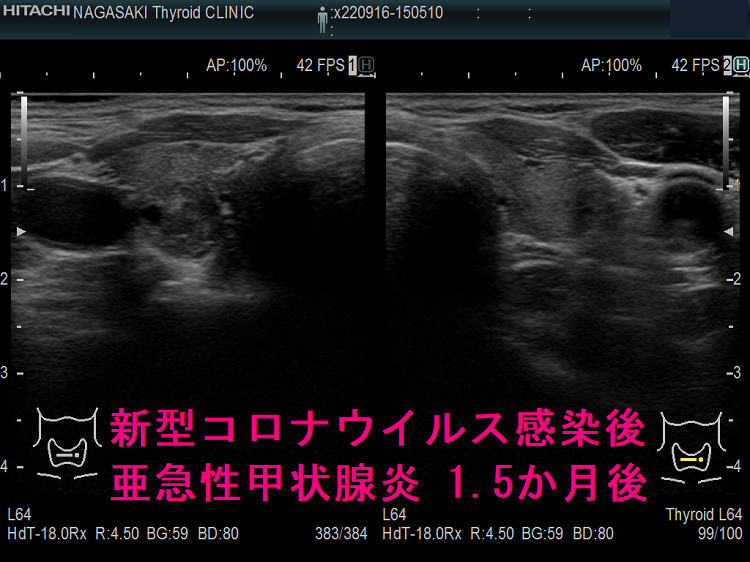

以下は、長崎甲状腺クリニック(大阪)の自験例です。

長崎甲状腺クリニック(大阪)の自験例

1.5か月後